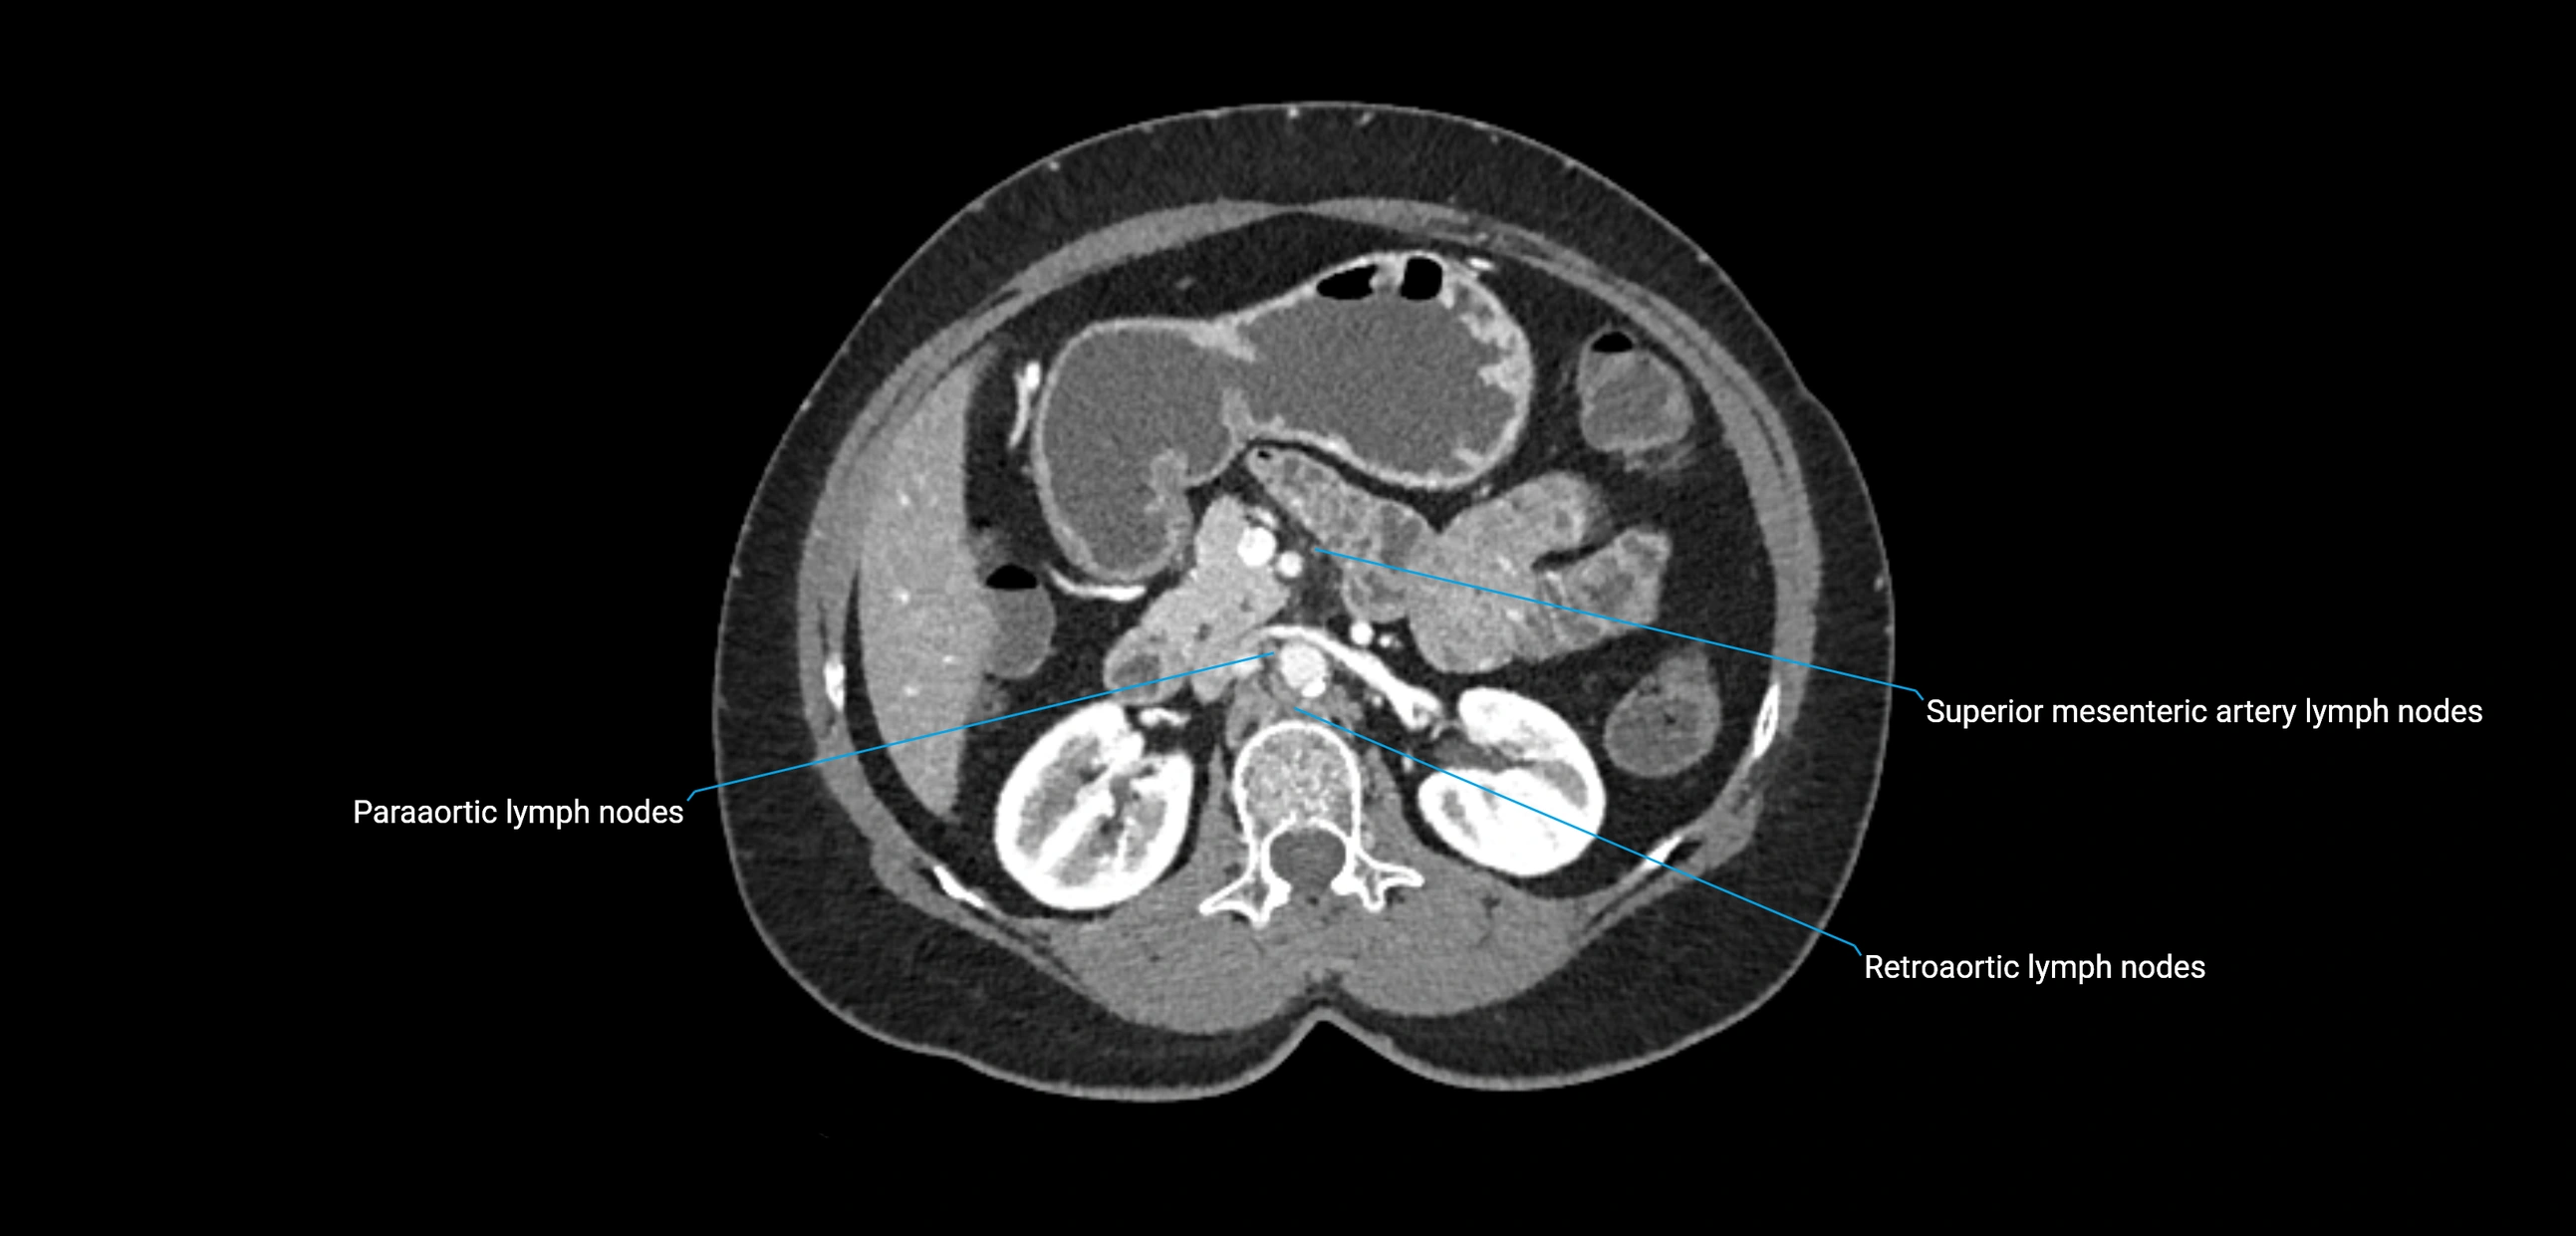

CT Appearance

CT Pre-Contrast:

• Nodes appear as soft-tissue density nodules adjacent to the aorta and IVC

• Calcification may be seen in chronic infections (e.g., tuberculosis)

CT Post-Contrast:

• Normal nodes enhance homogeneously

• Malignant nodes may show heterogeneous enhancement, central necrosis, or conglomerate formation

• Size >1 cm short axis is suspicious, though morphology and distribution are equally important

CT Venography (CTV):

• Demonstrates nodal encasement or compression of adjacent vessels (aorta, IVC, renal veins)

• Useful in staging testicular and ovarian malignancies

• Provides 3D reconstructions for retroperitoneal lymph node dissection planning

CT image

image